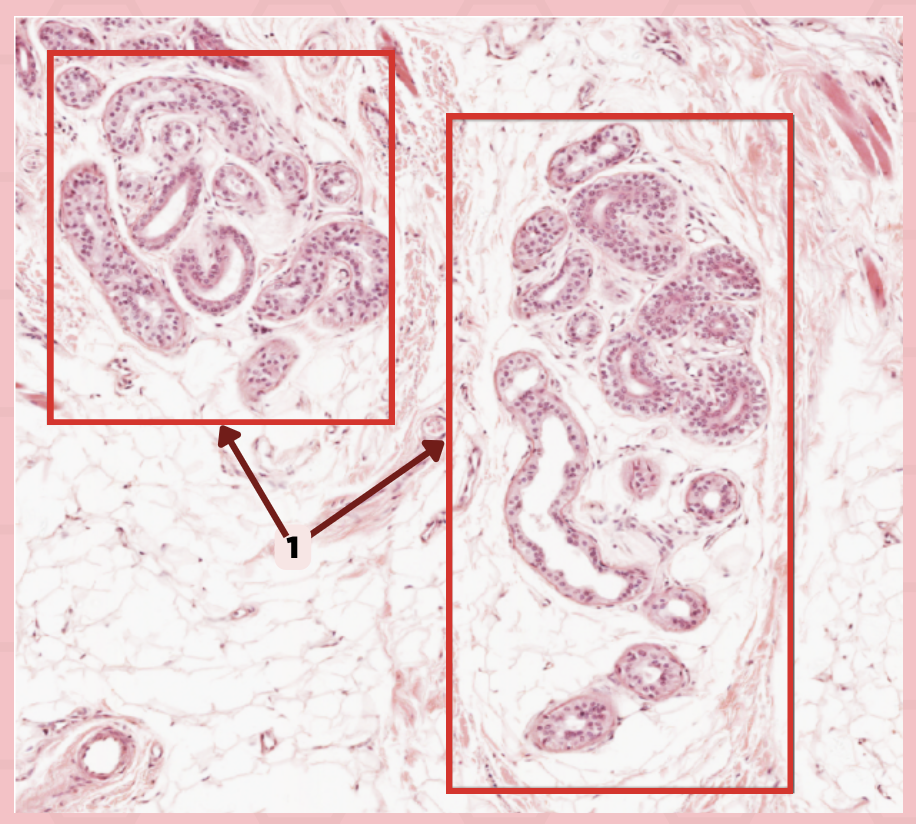

Submandibular

Identify the specimen.

Capsule

Identify the structure labeled as 1.

Septa

Identify the structure labeled as 2.